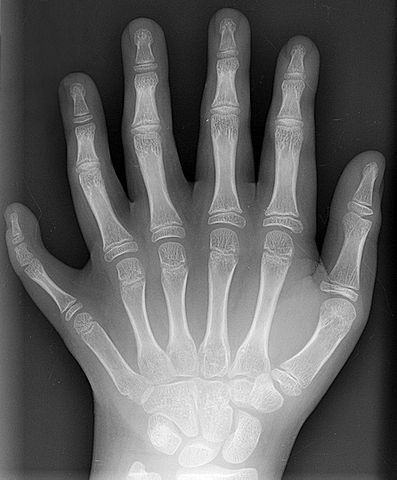

English: Conversion of a DICOM-format X-ray from a ten year old male showing polydactyly. This is the patient's left hand, posterior-anterior projection. Identifying tags and such have been stripped.

English: Conversion of a DICOM-format X-ray from a patient of en:User:Drgnu23, a ten year old male. This is the patient's left hand, posterior-anterior projection. Identifying tags and such have been stripped. The image is his, released under the GFDL. The image was subsequently altered by en:user:Grendelkhan, en:user: Raul654, and en:user:Solipsist.

Français : Radiographie de la main gauche (projection postérieure-antérieure) d'un jeune patient (10 ans) de Drgnu23 présentant une polydactylie.